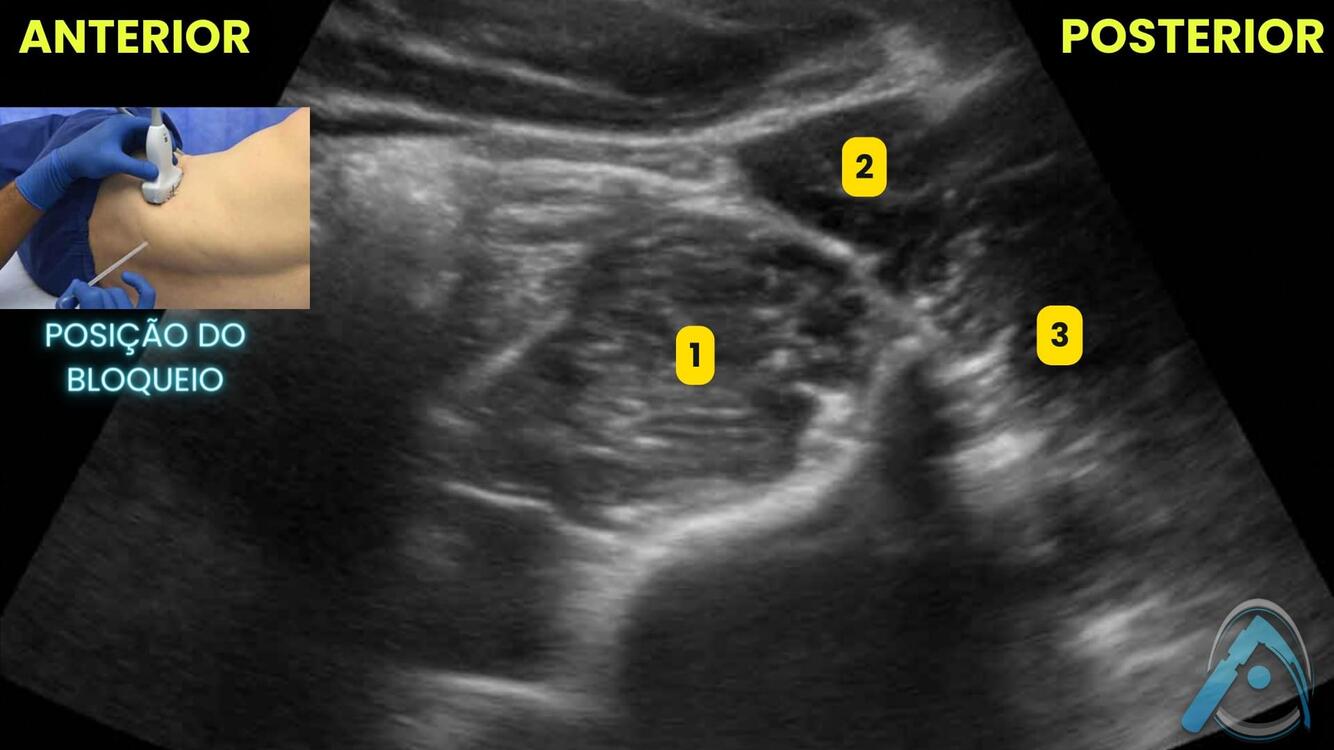

Você já viu o bloqueio do plexo sacral guiado por USG? Identifique as estruturas em destaque:

A

1 - glúteo máximo;

2 - piriforme;

3 - plexo sacral